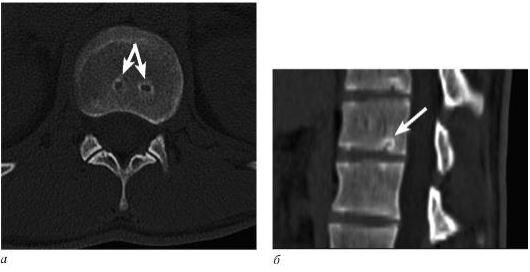

Узел Шморля при КТ визуализируется как очаг в губчатом веществе тела позвонка, прилежащий к замыкающей пластинке, плотностью +50...+60 HU, окруженный ободком повышенной до +250...+300 HU плотности.

Рис.1. КТ поясничного отдела позвоночника в аксиальной (а) и MPR-реконструкции в сагиттальной плоскости (б). Узлы Шморля. Нарушение целостности замыкательной пластинки тела позвонка.